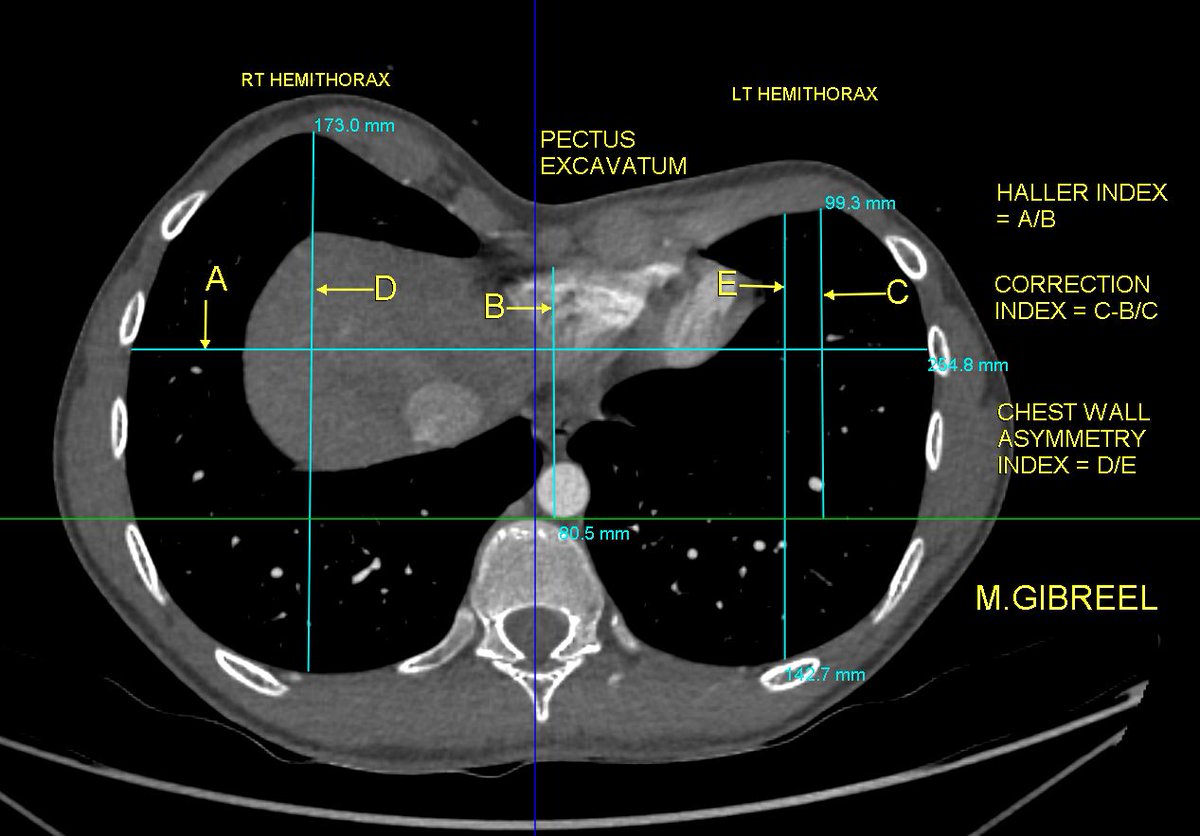

Pectus excavatum ,,, what to u need to be commented in your report ... From my archieve @AlkashkariWail

MGibreel1's tweet image. Pectus excavatum ,,, what to u need to be commented in your report ...

From my archieve

@AlkashkariWail